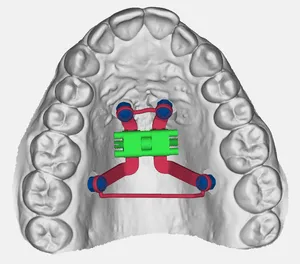

Arco Linguale

Dispositivo ortodontico indicato per mantenere gli spazi di eruzione in pazienti in fase di permuta della dentatura. Realizzato con tecnologia CAD-CAM, garantisce precisione unica e comfort ottimale per il paziente.